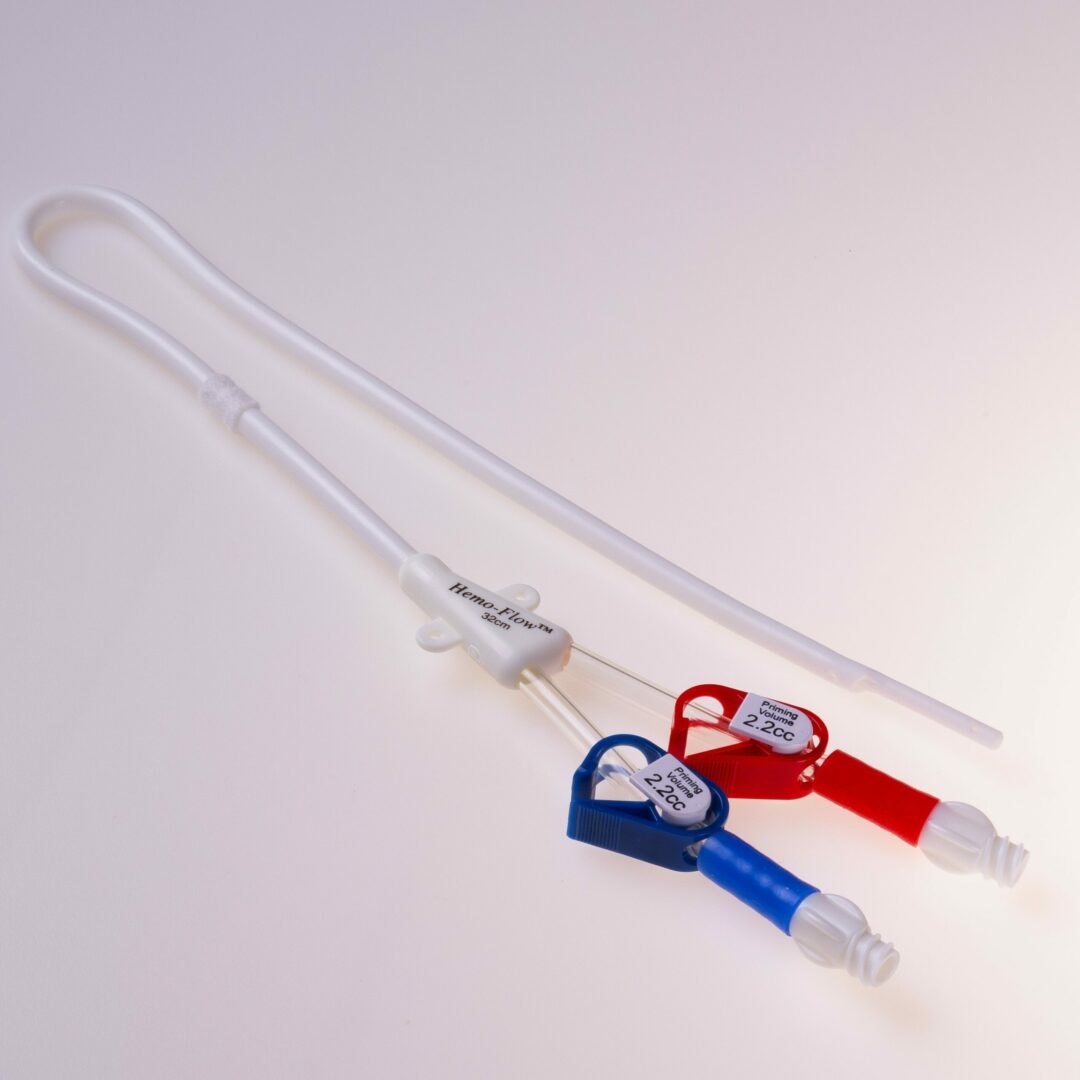

Der HFS Hemo Flow® ist ein untertunnelter Langzeitdialysekatheter für die chronische Hämodialyse. Er ermöglicht einen mehrjährigen, verlässlichen Gefäßzugang im Dialysebetrieb.

Der HFS Hemo Flow® ist ein untertunnelter Vorhofkatheter für die chronische Hämodialyse.

Der HFS Hemo Flow® wird antegrad untertunnelt. Die Einführung in das Gefäß erfolgt über eine Splitkanüle mit Schleuse.